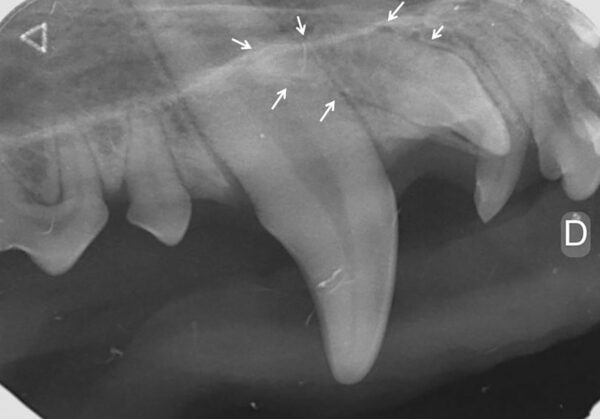

Para el diagnóstico de la EP, además de realizar un examen periodontal a través del sondaje debemos apoyarnos en la radiografía, ya que nos proporciona información acerca de la cantidad de pérdida ósea existente, así como del patrón que sigue esta pérdida (horizontal y/o vertical). En dientes multirradiculares, podemos servirnos de la furca para evaluar la pérdida de hueso, ya que aparecen áreas radiolúcidas bajo la bifurcación radicular a medida que se produce la destrucción ósea.

De acuerdo a esta pérdida del hueso alveolar detectada a nivel radiológico, clasificaremos la EP en cuatro grados:

- Grado 1 (PD1): sin pérdida ósea.

- Grado 2 (PD2): pérdida del soporte óseo menor al 25 % (imagen 7).

- Grado 3 (PD3): pérdida del soporte óseo de un 25-50 % (imagen 8).

- Grado 4 (PD4): pérdida del soporte óseo mayor de un 50 % (imagen 9).

Además de permitirnos evaluar el grado de enfermedad periodontal, también hace posible seleccionar el mejor tratamiento en función de su patología y las posibles complicaciones, como las fracturas mandibulares iatrogénicas en perros de talla pequeña con enfermedad periodontal PD4 (imágenes 10 y 11).